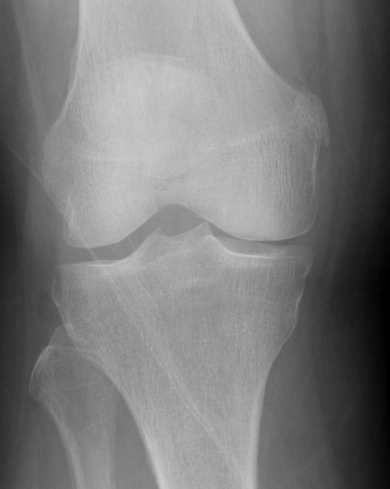

Pellegrini-Stieda Lesion

- calcification at insertion of femoral MCL

- indicative of chronic injury